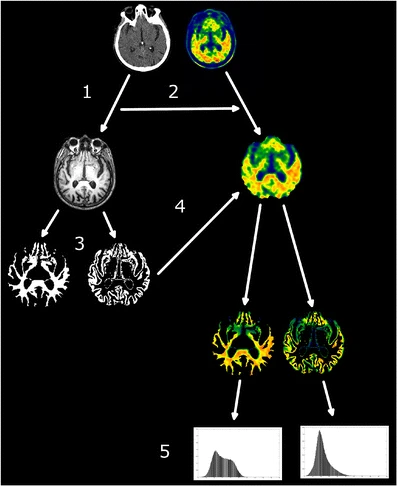

Grace à l’association entre IRM morphologique et TEP amyloïde j’ai pu extraire les histogrammes de charge amyloïde dans la matière blanche et grise des patients Alzheimer et témoins. Une analyse multivariée des index issue des histogrammes de la matière blanche a montré, pour la première fois, que la fixation d’amyloïde dans la matière blanche est en relation avec la pathologie (Nemmi et al., Eur J Nucl Med Mol Imaging, 2014).

L’association d’IRM et TEP a aussi permis de montrer que si une normalisation spatial directe de données de TEP amyloïde sur un template est plus adapté pour l’utilisation clinique, la registration de données TEP sur l’IRM est plus adapté pour la recherche (Saint-Aubert*, Nemmi*, et al., Eur J Nucl Med Mol Imaging , 2014).

Illustration d’une méthode de registration directe et via le CT scan et l’IRM de l’imagerie PET amyloïde